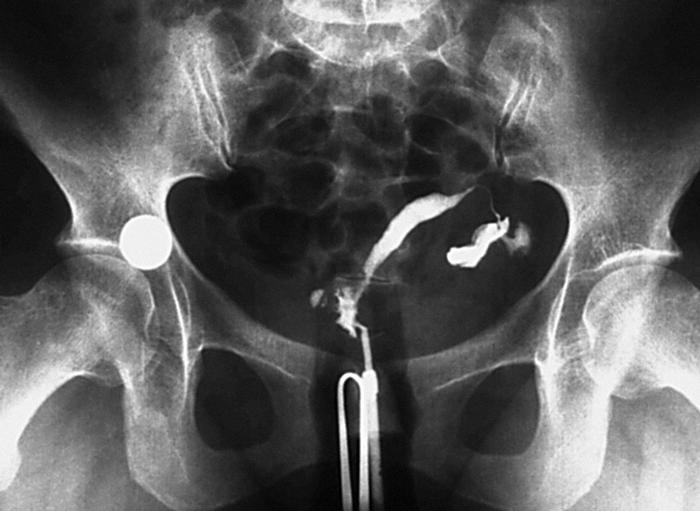

Tuve una epi. Me hicieron una lamparoscopia para tratar la infección. Posteriormente en una histerosalpinpografia presente una trompa con escaso relleno sin salida de contraste a peritoneo y otra de calibre normal, permeable y con salida de contraste a peritoneo. La trompa funcional es la izquierda. Puede lograrse el embarazo con una sola teompa?

La mejor forma de saber si una mujer se puede quedar embarazada es probándolo. En tu caso, con el antecedente de la EIP y el resultado de la histerosalpingografía, es probable que encuentres dificultades. Por eso mi recomendación es intentarlo unos 4 meses y si no hay éxito acudir a un centro especializado para hacer un tratamiento por el problema tubárico.